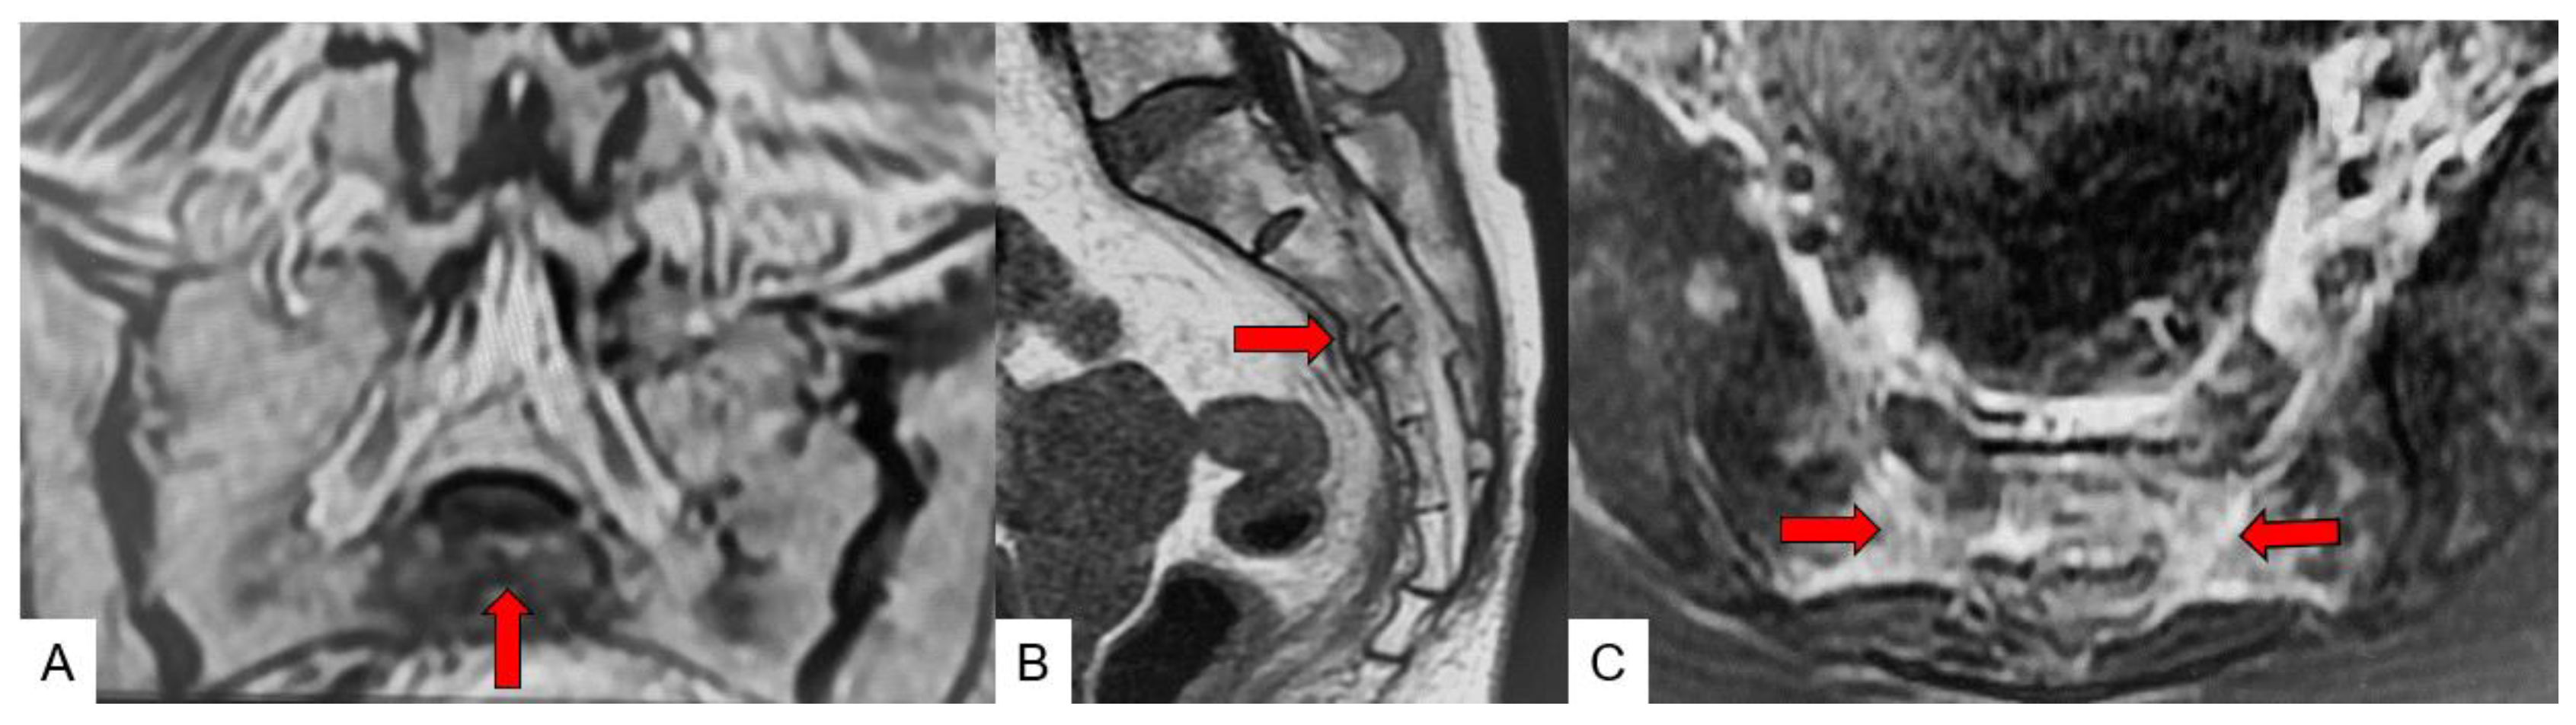

3.3. SIF Fracture Pattern

3.4. Typical SIF Case